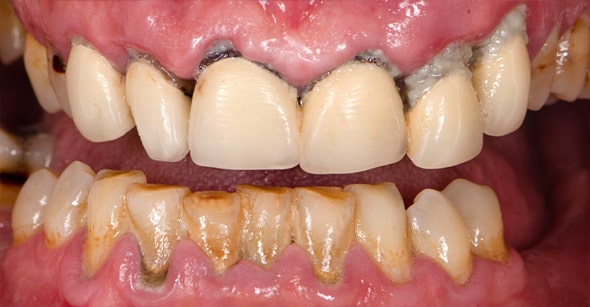

ボロボロのお口を劇的に改善

「オールオン4+α」という選択

重度歯周病・総入れ歯から

解放され、あなたの笑顔を取り戻す

オールオン4+α(All-on-4+α)とは、上下に最少4本ずつのインプラントを埋入し、総入れ歯の形をした上部構造を固定して短時間で見た目と噛み合わせ機能を回復させる治療法です。

長い間歯がない状態が続くと、歯を支える骨がなくなっていきます。そうなってしまうと通常のインプラント治療が難しくなります。そんな状態でも、傾斜埋入という技術で斜めにインプラントを埋入して上部構造をガッチリと固定することができるため、歯がボロボロの方や骨の少ない方のように多くの患者さまの状態に適用することができます。